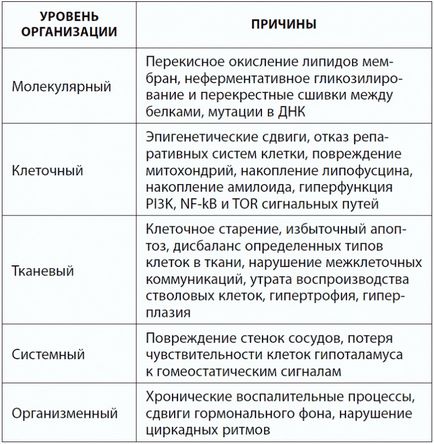

Причини старіння (з книги "120 років життя - тільки початок. Як перемогти старіння?")

Якщо міркувати філософськи, у старіння дійсно одна причина: недосконалість пристрої живого організму. Згідно з ідеєю професора Гарвардської школи медицини Вадима Гладишева, деяка кількість помилок в роботі живих систем долає всі захисні бар'єри, накопичується і викликає старіння. Єдиний спосіб уповільнити старіння, як він вважає, - уповільнити наш метаболізм. Пітерський вчений Олексій Голубєв дотримується подібних поглядів: в тканинах при обміні речовин постійно відбуваються побічні реакції, в результаті акумулюються помилки метаболізму, що призводять до старіння.

Однак «недосконалість» - занадто загальна причина. Більш конкретні фактори старіння умовно можна розділити на чотири великі групи (рис. 3): це гени, в тому стані, в якому вони нам дісталися у спадок (генетика); це рівень активності генів в кожній тканини (епігенетика); це діючі на нас фактори навколишнього середовища - їжа, клімат, якість повітря і води; і, нарешті, наше старіння додатково визначається випадковими збоями. В результаті дії цих причин відбувається відхилення живої системи від оптимального режиму функціонування, тобто порушення гомеостазу. Вченим відомо безліч видів таких відхилень: це і окислювальні реакції під впливом вільних радикалів, і розриви хімічних зв'язків під дією води, і порушення структури різних молекул під впливом тепла і хімічних речовин (наприклад, шкідливе взаємодія білків і глюкози), їх пошкодження іонізуючоїрадіацією і ультрафіолетом і злипання деяких білків з утворенням внутрішньоклітинного і позаклітинного сміття, і нестача деяких речовин, збої в регуляції фізіологічних процесів і невиправлених в ДНК ... Мн ожество маленьких, але дуже шкідливих випадковостей, накладаючись один на одного, поступово підточують наше здоров'я. Системи підтримання сталості внутрішнього середовища (гомеостазу) самі згодом розхитуються, тому з віком фізіологічні функції все далі відхиляються від оптимуму. Якщо гомеостаз не відновлено, виникає патологічний процес, який збільшує ризик загибелі організму. Саме такі патологічні процеси ми називаємо вік-залежними хворобами.